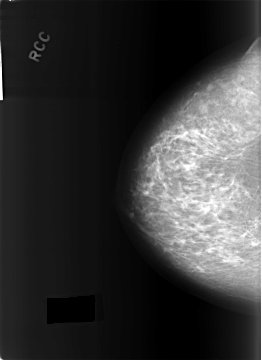

C_0288_1.RIGHT_CC

RIGHT_CC LINES 5760 PIXELS_PER_LINE 4192 BITS_PER_PIXEL 12 RESOLUTION 50 NON_OVERLAY